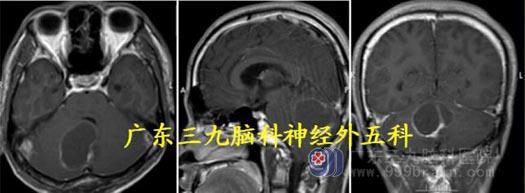

头颅MR:右侧小脑半球占位性病变呈大囊小结节改变,范围约58×42×49mm,边界尚清,增强后病变实性病变呈明显强化,其内间隔示线样轻度强化,囊性部分未见强化。考虑血管母细胞瘤合并幕上梗阻性脑积水、小脑扁桃体下疝;